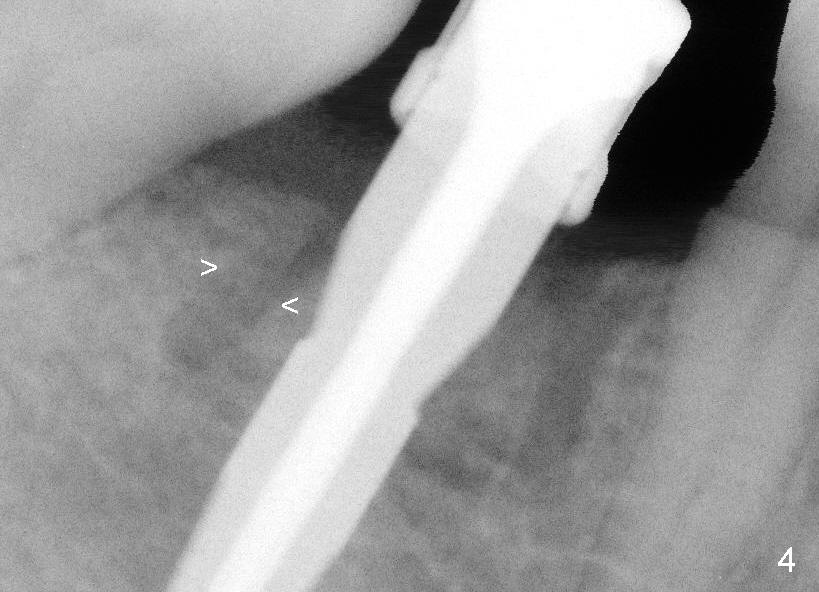

Sequential osteotomy does not seem to change the position of the buccal plate (Fig.3 (after 2 mm pilot drill), Fig.4 (4.1x12 mm drill).

Since the bone feels not dense during osteotomy mentioned earlier, a 4.5x12 mm submerged implant is placed without further osteotomy (Fig.5). It looks like that the buccal plate moves distally (arrow, as compared to arrowheads in Fig.4). There is a bony defect mesially (*), where bone graft is placed later.